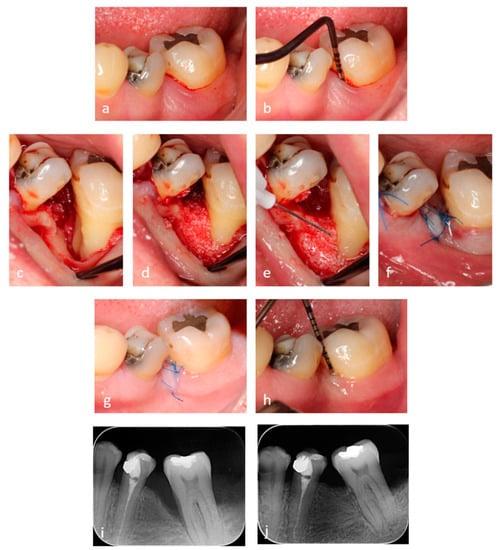

2.3. Surgical Procedures

2.4. Application of the Hyaluronic Acid (HA) and Xenograft